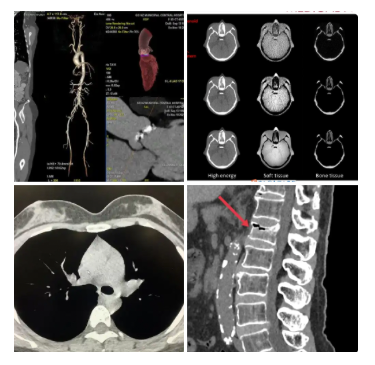

完美的图像质量

脊椎三维

• 信息丰富,利于诊断

内耳检查

内耳畸形

如Mondini畸形(耳蜗发育不全)、大前庭导水管综合征等,是儿童感音神经性聋的重要病因。CT可明确畸形类型,为人工耳蜗植入提供关键解剖依据

胆脂瘤或中耳炎累及内耳

慢性中耳炎或胆脂瘤可能侵蚀内耳结构,导致眩晕、听力骤降。CT能判断骨质破坏范围,评估是否出现瘘管(如半规管瘘

颞骨骨折

头部外伤后,横行骨折易损伤耳蜗、前庭,导致感音神经性聋。CT是诊断骨折线走向及内耳受累的金标准

听神经瘤等占位性病变

虽MRI更优,但CT可显示内听道是否扩大、骨壁是否破坏,作为初步筛查手段